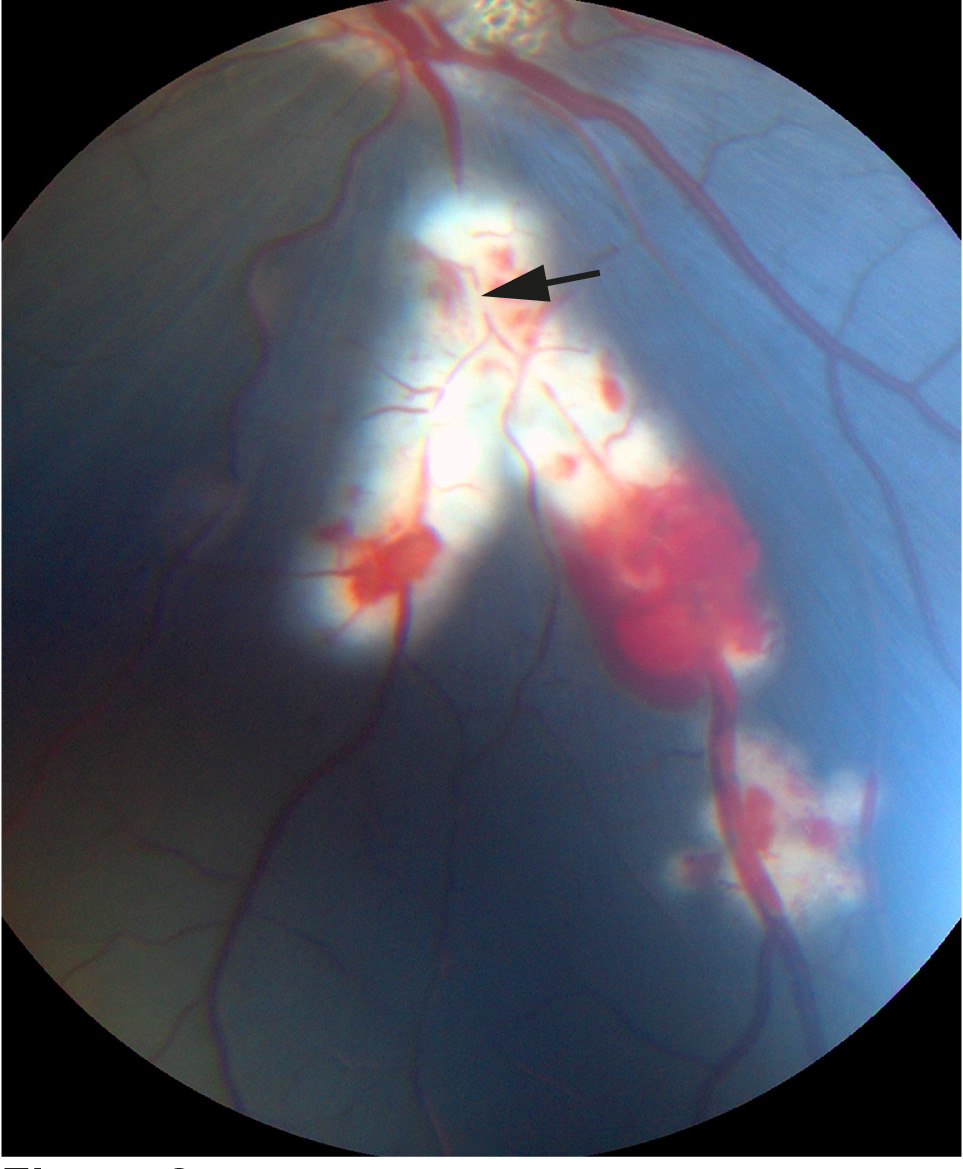

Figure 2. Fundus image of BRVO obtained approximately 10 min after BRVO in the inferior retina. Branch retinal vein occlusion (BRVO)

was considered successful when venous dilation and hemorrhages were observed upstream of the site of occlusion as seen in

the image. Black arrow: site of occlusion.